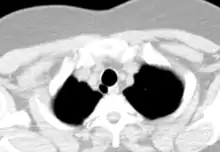

- CT scan of the thorax (axial lung window)

- CT scan of the thorax (coronal lung window)

- CT scan of the thorax (coronal mediastinal window)